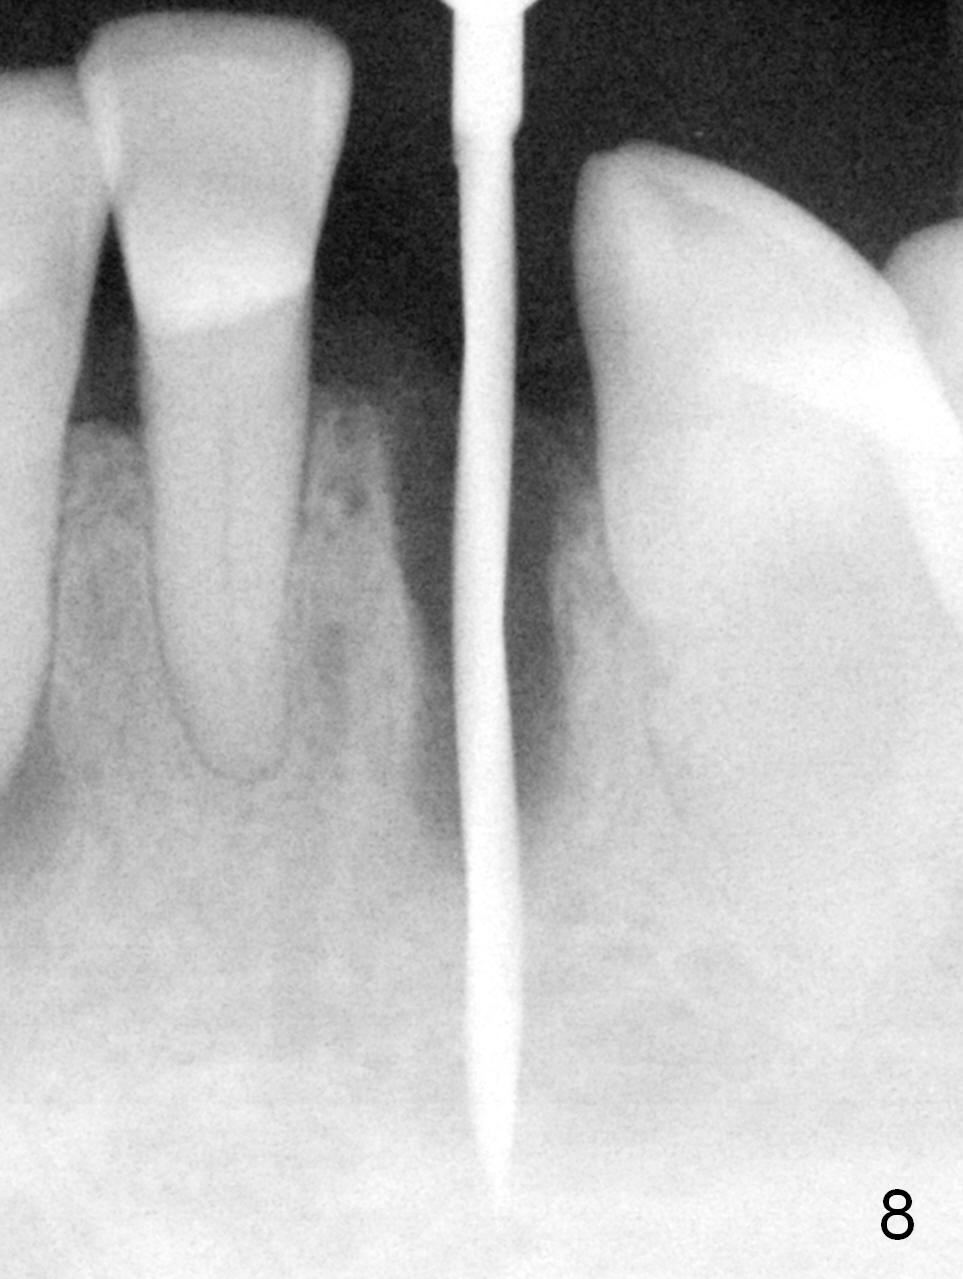

A 74-year-old man has several missing teeth (Fig.1). His 1st goal is to replace the lower left lateral incisor (Fig.2). The residual root has an apical lesion (Fig.3 *). To describe intraop findings, a CT image of a different patient is used (Fig.4 coronal section; B: buccal; L: lingual). After extraction, the buccal plate is found to be thin and low (Fig.5 arrowheads). A 1.5 mm pilot drill (Fig.6 red line) is used to initiate osteotomy in the lingual plate of the socket. Once the drill penetrates the lingual plate, the trajectory changes and the depth is 17 mm from the gingival margin (Fig.7). A PA is taken (Fig.8); it appears that the osteotomy can be extended more apically. When the pilot drill extends to 20 mm, there is sudden empty feeling. The lingual plate has perforated (Fig.9). A new osteotomy is established buccally (Fig.10 pink). To avoid buccal plate perforation, especially in the buccal undercut area (>), the coronal end of the drill has to be tilted buccally (<--). An angled abutment (3x20 mm, 15°) is placed (Fig.11,12). The abutment is modified (Fig.13,14) to accommodate an immediate provisional (Fig.15,16 P). Perio dressing is to be applied to prevent the bone graft from getting dislodged buccally (Fig.15). The dressing is in place 7 days postop (Fig.17).